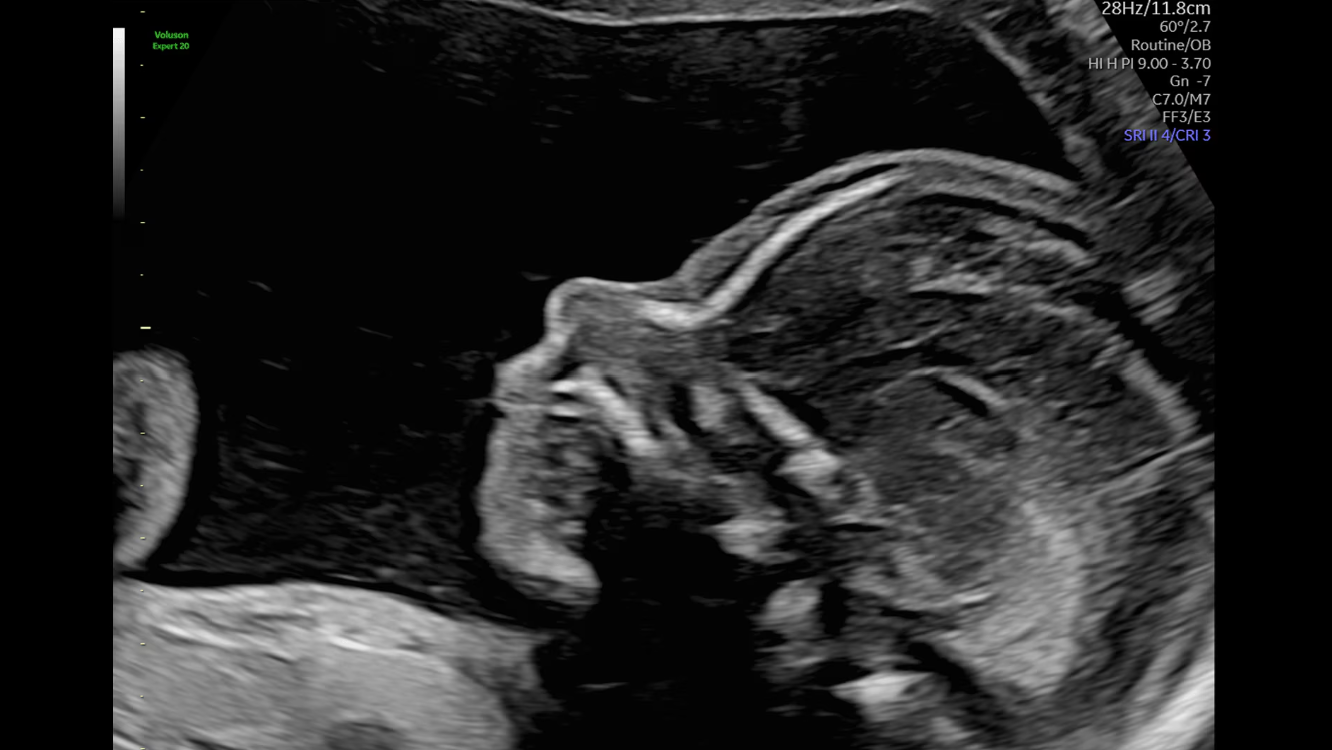

Профиль плода на 21 неделе